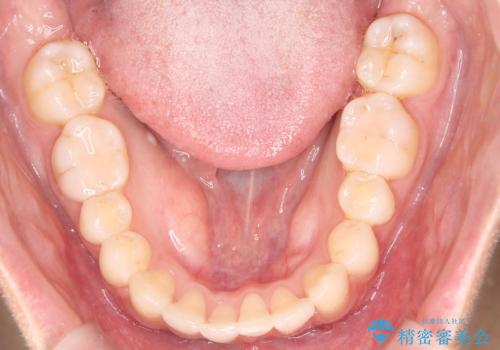

治療計画をしっかり立て、歯の移動量や力のコントロールを最適化することで、約1年という短期間で矯正治療を終了することができました。

「矯正は時間がかかる」というイメージをお持ちの方も多いですが、症例によっては、非抜歯でも短期間で改善が可能な場合があります。

治療後は歯並び・かみ合わせともに大きく改善し、患者様にも大変ご満足いただけました。